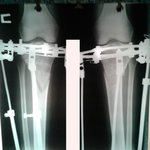

Исходник - 35 лет.

Укорочение правой ноги - 2 см.

Левая голень более деформирована.

Дата операции 22.03.2016г.

Дата снятия аппаратов 22.06.2016г.

Срок лечения 90 дней.

Диагноз: Укорочение правой ноги - 2 см.